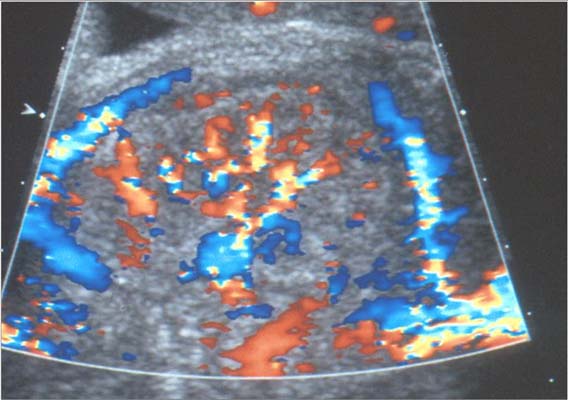

Tumeur de Bolande